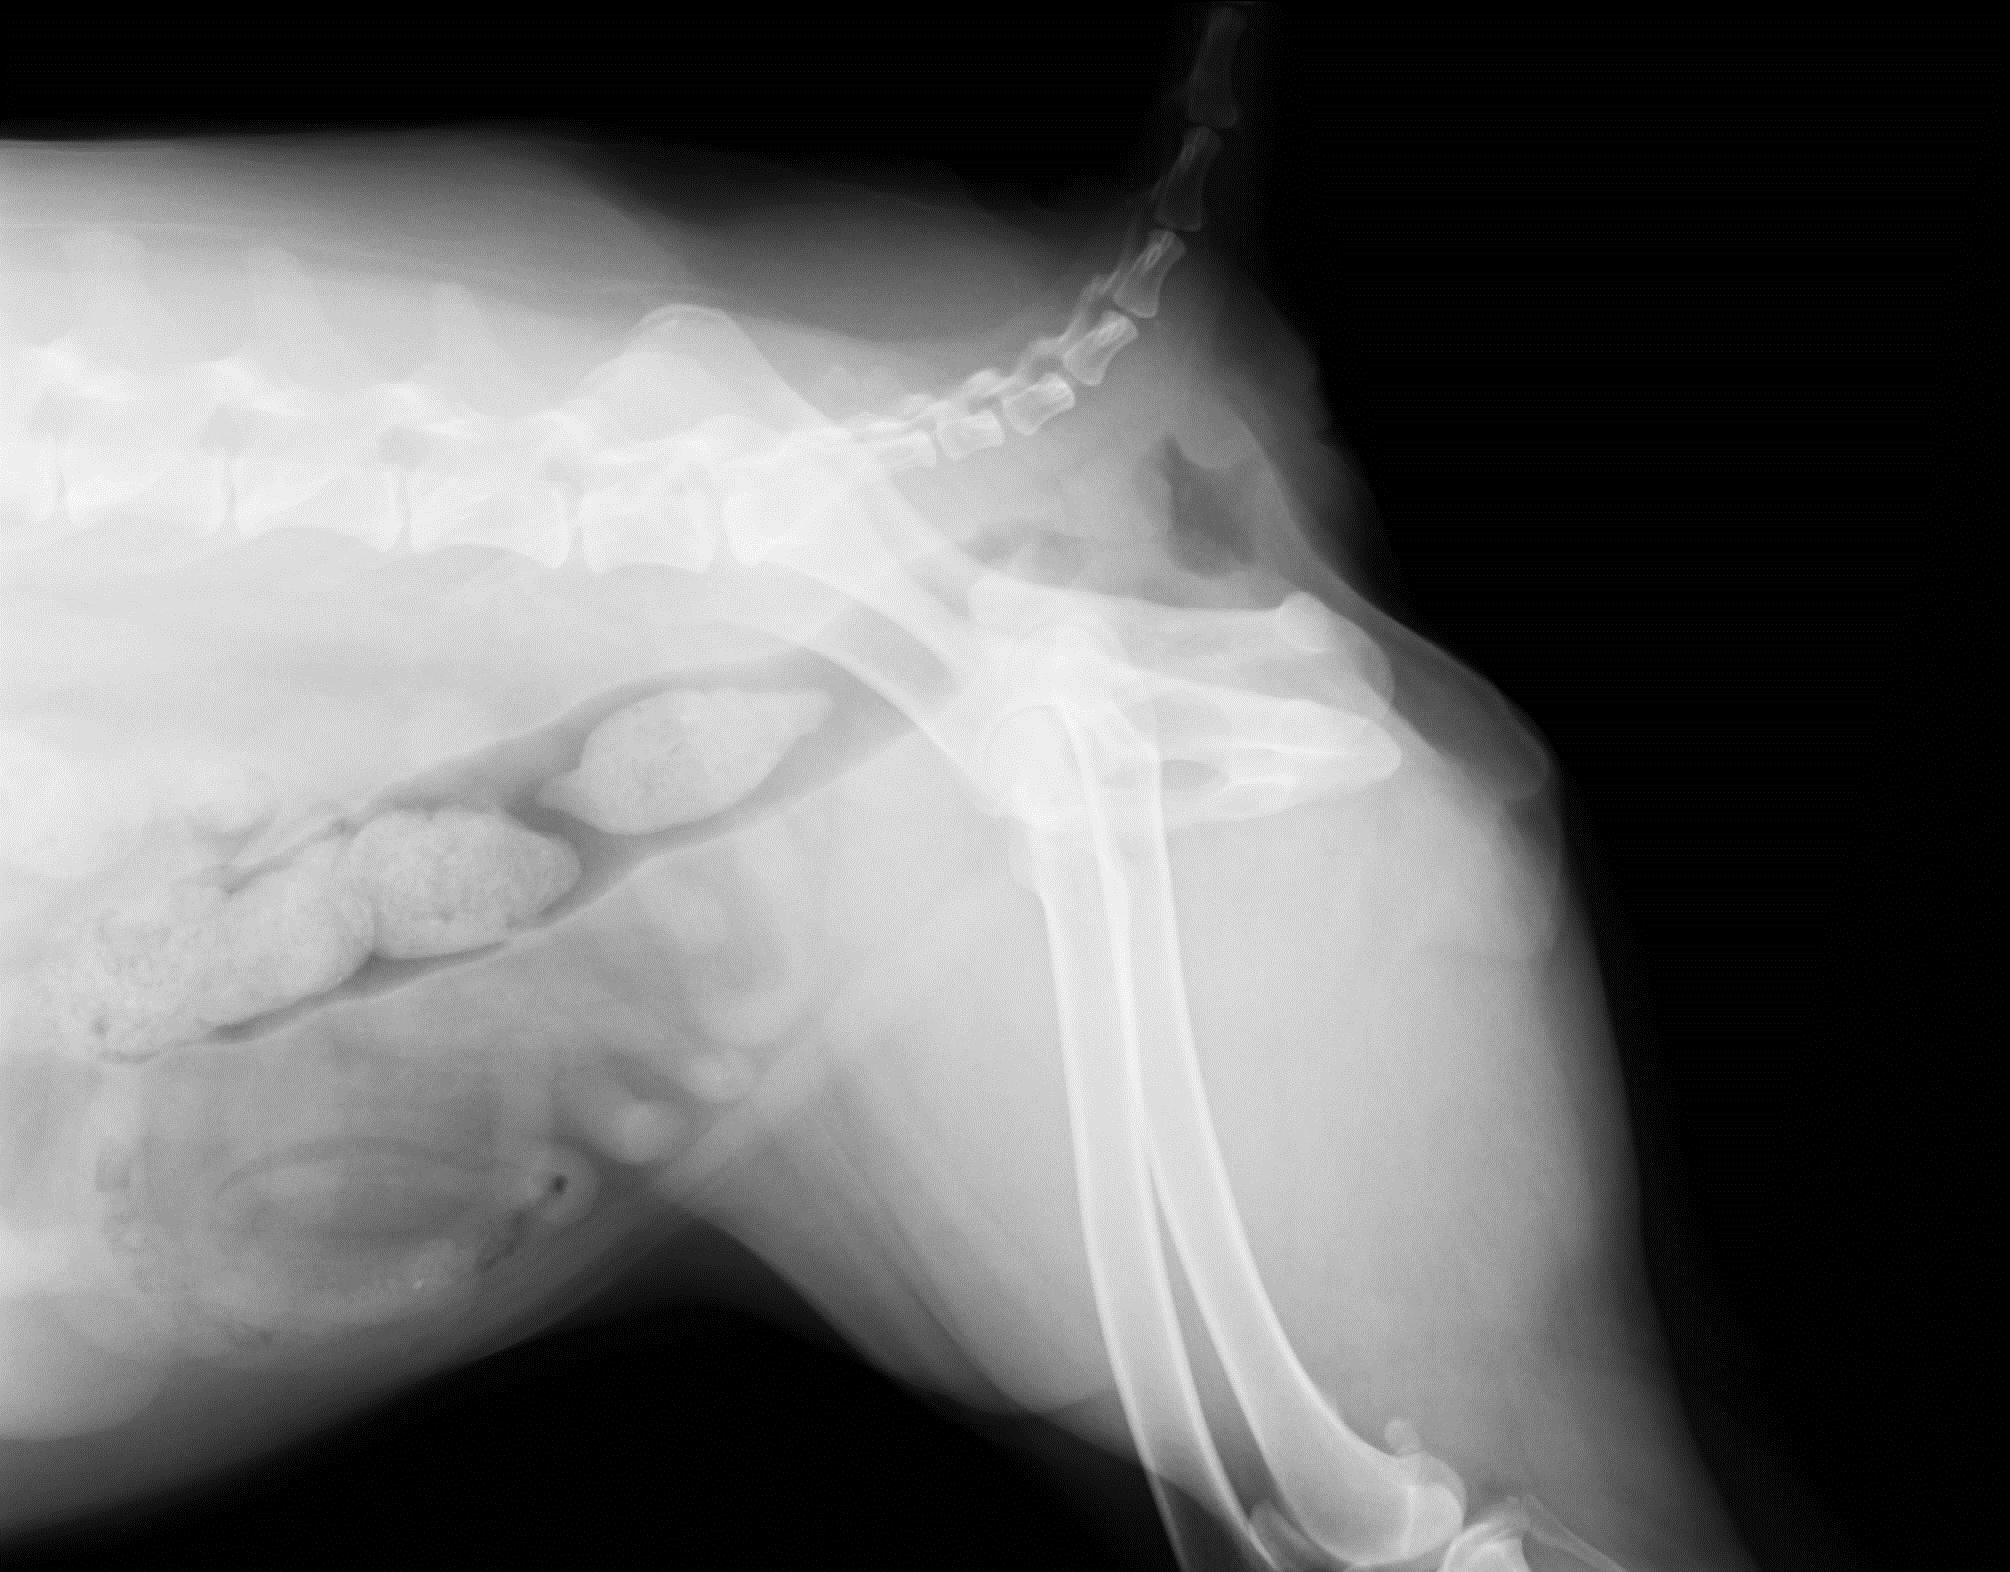

主訴:近隣の動物病院からのご紹介症例で、2週前から排便ポーズをとっても便がでない状態になり、直腸検査にて直腸に腫瘤が触知されため当病院に受診されました。レントゲン検査、大腸内視鏡検査にて、直腸領域に多発性の腫瘍が認められました。